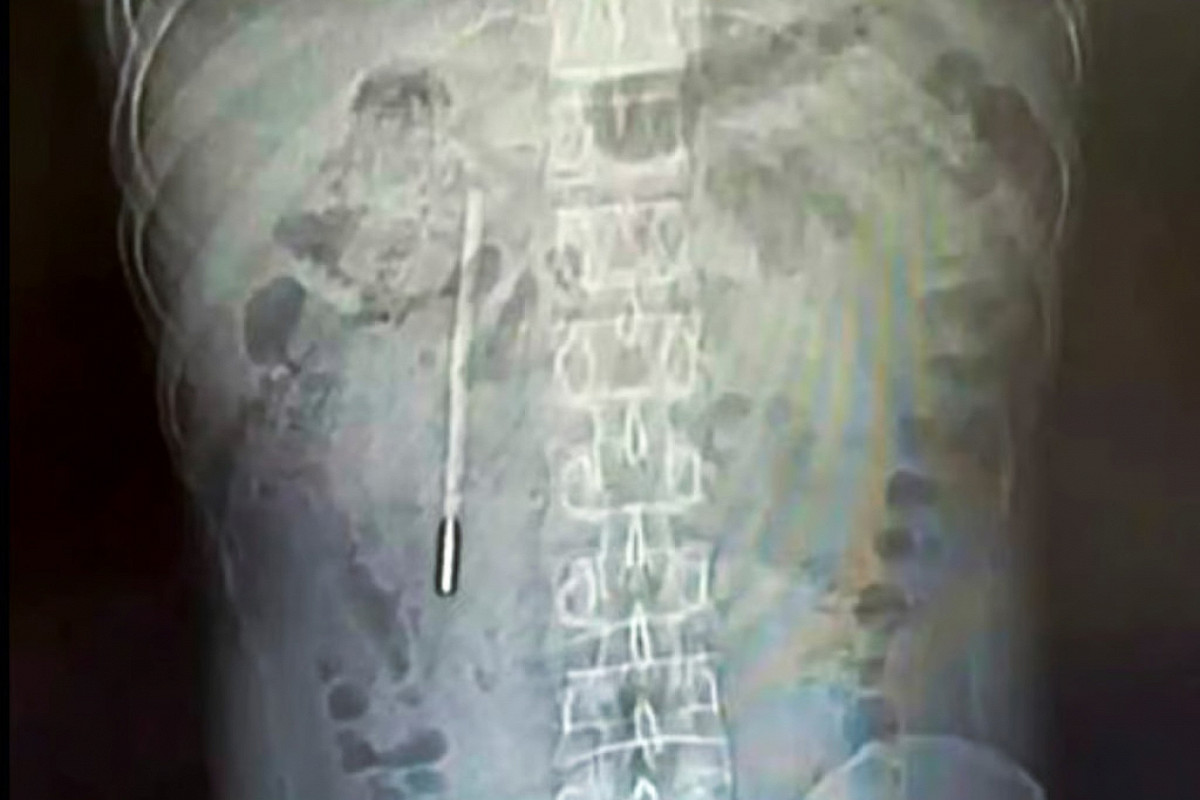

Градусник застрял в двенадцатиперстной кишке пациента. Кончик предмета прижался к стенке кишечника и угрожал привести к перфорации и сильному внутреннему кровотечению, так что медики немедленно извлекли термометр.

Его удалось извлечь целым и неповрежденным. Однако врачи отметили, что показания о температуре стерлись.